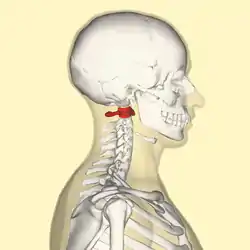

Position of the atlas shown in red | |

In anatomy, the atlas (C1) is the most superior (first) cervical vertebra of the spine and is located in the neck.